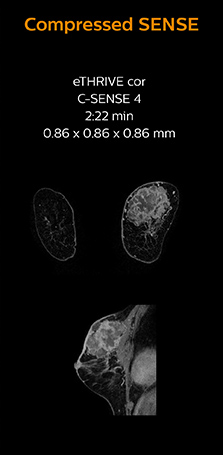

Ingenia 1.5T MRI scans with and without Compressed SENSE are compared for this case of a hip with a synovial cyst. In the mDIXON sequence, the Compressed SENSE factor used is higher than the SENSE factor on the previous scan, so scan times are reduced without sacrificing image quality. The high resolution images are useful for diagnosing of a detailed dissection. The diffusion TSE with Compressed SENSE shows reduced noise compared to the Diffusion TSE with SENSE and the artifact has disappeared.

So in this case, Compressed SENSE helped in reducing scan times of the examination. The Compressed SENSE images allowed the radiologist to confidently diagnose the lesion and see the anatomic relationships of the abnormal signal to the surrounding structures.

In this MRI exam of pelvis in a patient with myoma, Compressed SENSE is used to accelerate individual sequences and thus the entire examination on Ingenia 1.5T. Compressed SENSE allowed for a decrease in scan time for the T2 TSE from 3:38 to 1:46 minutes. The Compressed SENSE images in this case show fewer motion artifacts than the images from the previous protocol with SENSE. In 3D PelvisVIEW, the Compressed SENSE images have a higher and isotropic spatial resolution with a scan time similar to the SENSE sequence. The improved spatial resolution and better contrast in the myometrium of the uterus allowed radiologist Dr. Koyama to confidently diagnose the cancerous lesion in the uterus. The use of Compressed SENSE accelerates scanning times and increases spatial resolution in 3D PelvisVIEW.